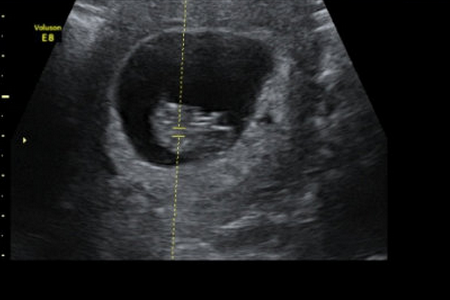

受精是精子穿入卵子形成受精卵的过程。受精一般发生在排卵后的12小时之内的输卵管壶腹部,整个受精过程大约需要24小时。

但是也要看天时,人排卵后约30小时,卵子小姐到达输卵管壶腹部并在此停留30小时,称“输卵管封闭”。此封闭控制和减少输卵管内的精子数量,为正常受精创造条件。

在千山万水人海相遇,原来你也在这里。发育正常并已获能的精子与发育正常的卵细胞在限定时间内相遇是受精的前提条件。